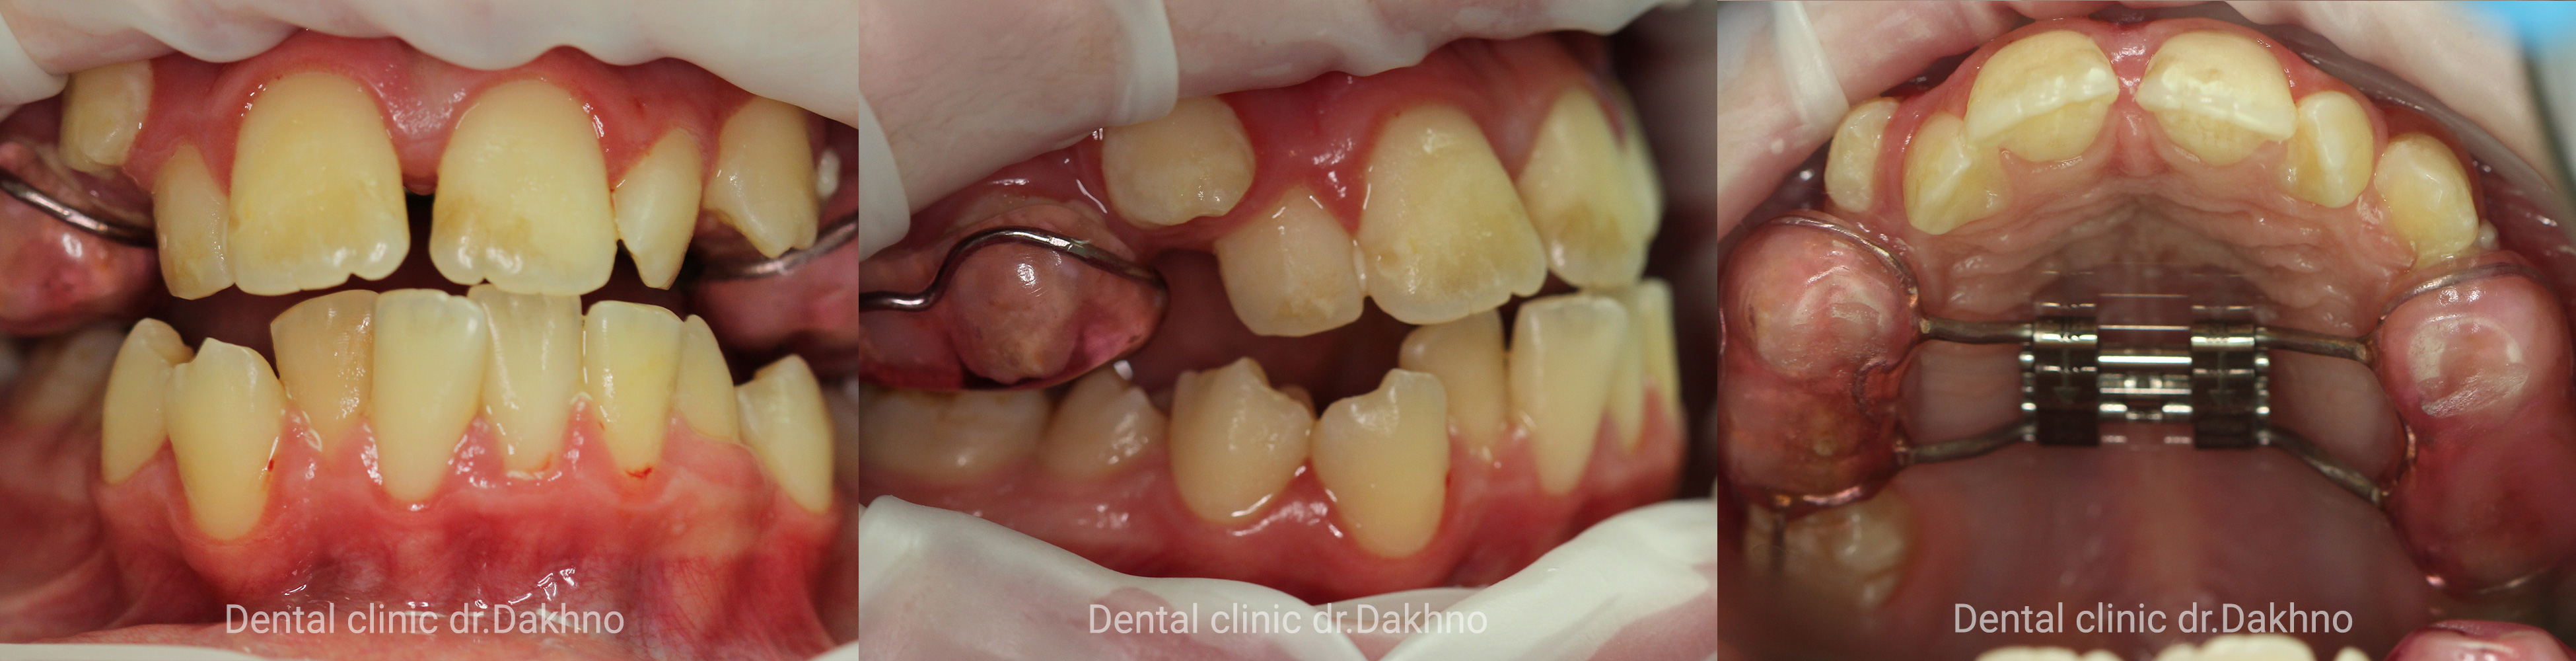

Липень 2017 Батьки звернулися в клініку з метою виправлення скученості зубів. Після отримання необхідних діагностичних даних: виконання КПКТ (конусно-променевої комп’ютерної томографії), фотопротокола і отримання діагностичних моделей прийнято рішення першим етапом ортодонтичного лікування виконати розширення верхньої щелепи за рахунок фіксованого апарату HYREX на оклюзійних накладках.

Жовтень 2017 По проміжному результату прийнято рішення доктором ортодонтом Мітюріною Тетяною Володимирівною почати ортодонтичне лікування нижнього зубного ряду за допомогою брекет системи.

Грудень 2017 Закінчено розширення і зафіксований гвинт на апараті HYREX

Квітень 2018 Знятий апарат HYREX з зубного ряду верхньої щелепи і зафіксована брекет-система на зуби верхньої щелепи.

Липень 2019 Незважаючи на складності стану і розвитку Амалія і батьки дуже відповідально ставляться до етапів лікування і гігієни, що дозволило доктору прийняти рішення щодо застосування еластиків. Завдяки їм не дивлячись на кісткову асиметрію вдалось досягти задовільних результатів.